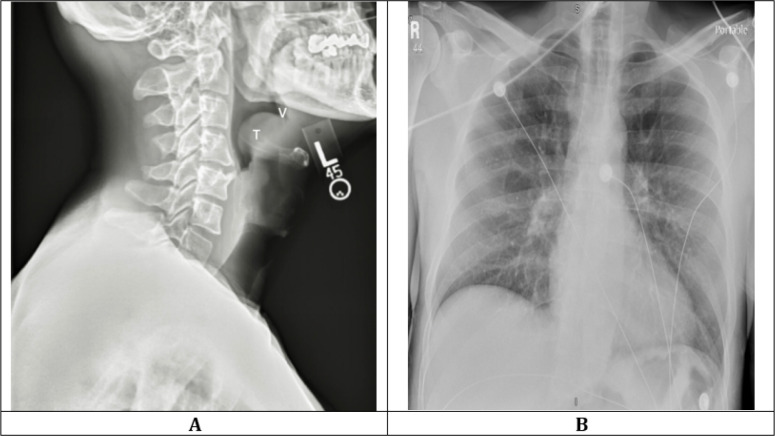

在实施乙型流感嗜血杆菌(Hib)疫苗接种后,急性会厌炎患者中大多数为成年患者。急性会厌炎表现为呼吸困难,必须迅速识别并采取干预措施,以防止气道受损和死亡。在此,我们介绍了一例 44 岁男性糖尿病患者的病例,他在咽喉疼痛和发热数日后出现急性呼吸急促和喘鸣。急诊科的评估结果显示,颈部软组织侧位 X 光片和鼻咽镜检查显示急性会厌炎的特征性体征。患者接受了静脉注射氨苄西林/舒巴坦和地塞米松的治疗,第 4 天出院回家。本病例强调,对于出现喘鸣和呼吸困难的成人,高度怀疑急性会厌炎至关重要。及时识别、气道管理和适当的抗生素治疗对于减轻与这种疾病相关的潜在破坏性后果至关重要。随着人口结构的变化和疫苗接种对流行病学的影响,在急诊环境中提高警惕对改善急性会厌炎成人患者的预后至关重要。

After the implementation of vaccination against Haemophilus Influenza Type B (Hib), adult patients comprise the majority of patients with acute epiglottitis. Its presentation with stridor mandates swift recognition and intervention to prevent airway compromise and mortality. Here, we present a case of a 44-year-old male with diabetes mellitus who presented with acute onset of shortness of breath and stridor following days of throat soreness and fever. Initial treatment for suspected anaphylaxis provided partial relief, and emergency department evaluation revealed characteristic signs of acute epiglottitis on lateral soft tissue neck x-ray and nasopharyngoscopy. Treatment was initiated with intravenous ampicillin/sulbactam and dexamethasone, and the patient was discharged home on day 4. This case underscores the critical importance of maintaining a high index of suspicion for acute epiglottitis in adults presenting with stridor and respiratory distress. Prompt recognition, airway management, and appropriate antibiotic therapy are paramount in mitigating the potentially devastating outcomes associated with this condition. As demographics shift and vaccination impacts epidemiology, heightened vigilance in emergency settings is essential to improve outcomes in adult patients with acute epiglottitis.